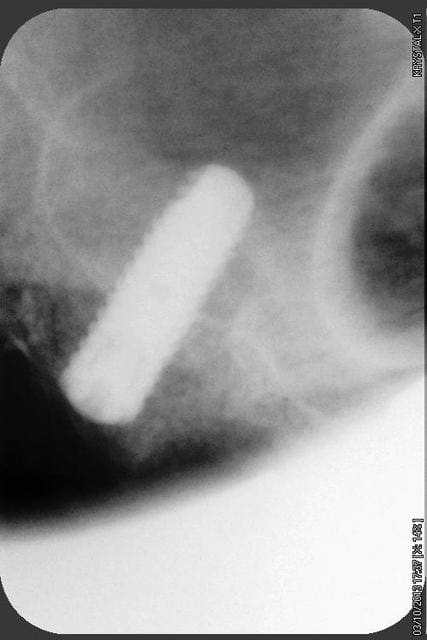

quelques radios.

oui, bien sur ce sont des Tatum D1 en bas et D4 en haut